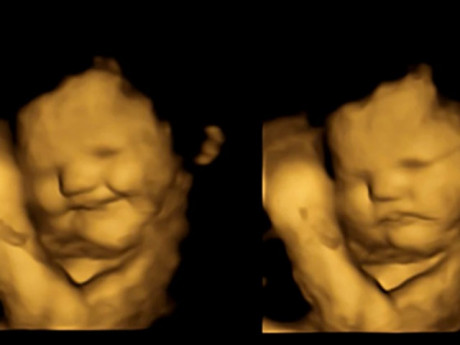

Ở tuần 36 thai kỳ, khuỷu tay, chân và đầu bé có thể nổi lên trên bụng của người mẹ khi bé “vươn vai” hay chuyển động. Khuôn mặt bé trông khá bầu bĩnh, một phần do các lớp mỡ và một phần do sự phát triển mạnh của các cơ mút.

Tóc bé có thể mọc dài đến 5 cm. Các móng tay, móng chân của bé cũng rất dài, vì thể bạn có thể sẽ phải cắt móng tay cho bé khi bé vừa mới chào đời.